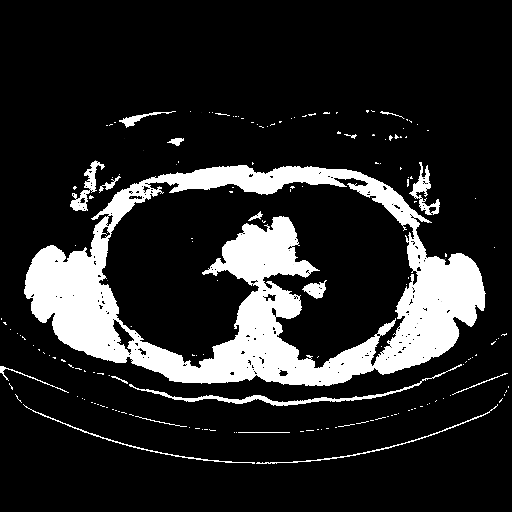

Image Grid

4Γ—3 grid: Rows show different image types (Original NATIVE, Reconstructed NATIVE, Original VENOUS, Generated VENOUS), Columns show windowing techniques (No Window, Lung Window, Mediastinum Window)

Original NATIVE CT scan (input)

Full window (WL 1023.5, WW 4095 β†’ Low βˆ’1024, High +3071)

Actual HU range: [-1024.0, 3071.0]

Reconstructed NATIVE CT scan (cycle consistency)

Original VENOUS CT scan

Generated VENOUS CT scan (A→B translation)